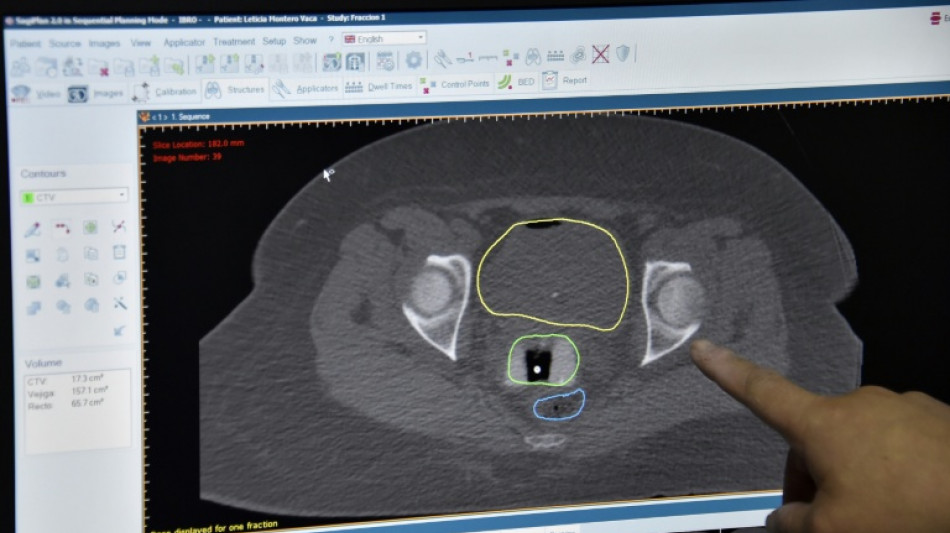

Improvements in cancer survival rates in England and Wales have slowed down significantly since 2010, according to a major study released Wednesday, leading to calls for an urgent national cancer plan.

The study, conducted by the London School of Hygiene and Tropical Medicine, measured the survival index for 10.8 million adults diagnosed with cancer between 1971 and 2018, accounting for variables like age, sex, and cancer type.

It found substantial improvements over the 48-year period, with the five-year survival index increasing from 28.8 percent in 1971–72 to 56.6 percent in 2018.

The 10-year survival index improved by four percent between 2000–01 and 2005–06 and only 1.4 percent between 2010–11 and 2015–16.

The slowdown since 2010 "is likely to be at least partly explained by longer waits for diagnosis and treatment," said the report.

The deceleration has been observed across many individual cancers, "implying a system-wide challenge," said the study, funded by the Cancer Research UK charity.

Most notably, the 10-year survival index for breast, cervix, rectum, prostate, testis, and uterus cancers plateaued in the last 10–15 years, while the index for larynx cancers decreased.

Pancreatic cancer survival, at 4.3 percent in 2018, has shown minimal change since 1971–72.

The study calls for a "new, long-term National Cancer Plan" to "bring cancer survival trends back towards the best in the world".